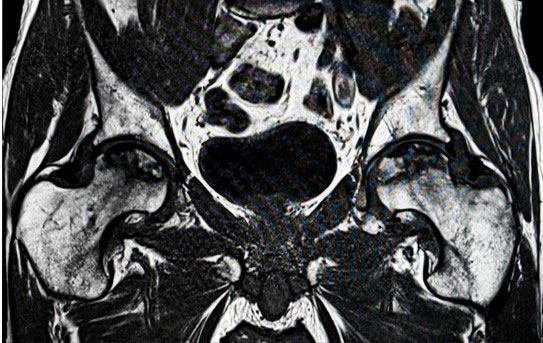

Secondary arthritis is a group of diseases that causes arthritis that is not classified as osteoarthritis or rheumatoid arthritis. Types of secondary arthritis include arthritis caused from avascular necrosis or prior fractures or trauma.

There are multiple other diseases which can cause arthritis such as psoriasis or people who are born with joint abnormalities such as congenital dysplasia of the hip. It is important to seek care from a fellowship trained specialist in joint replacements or Adult Reconstruction as these orthopaedic surgeons will be best to treat pain associated from secondary arthritis.